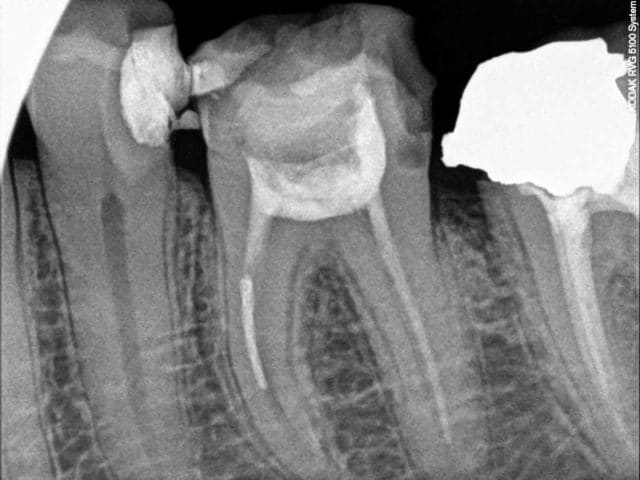

Patient vus à un mois d'intervalle pour des douleurs. Pas de devis miroboland, des CCM à 500 euros qui feront plaisir à santéclair ou à notre ministre de la mauvaise santé, secteur campagne.

Vus la premiere fois pour un debut d'infection sous 47 un samedi à la fermeture, demontage du screw post, allésage laissée ouverte avec une prescription puis retours chez mon confrére.

Puis un mois plus tard retour un samedi pour des douleurs suite à l'obturation de 46, endo metasonne, cône de 2%, canal ML et DL non preparés, démontage du cône DV avec le coton laissé dans la chambre.

Il n'ai pas besoin de faire des devis delirant ou de partiquer des tarifs de prothése excessifs pour mal faire notre travail.

Il a l'air doué ce dentiste ... il aurait pu faire la couronne sans faire l'endo sur la 6 et on fait semblant de pas avoir vu la fracture d'instrument sur la 7